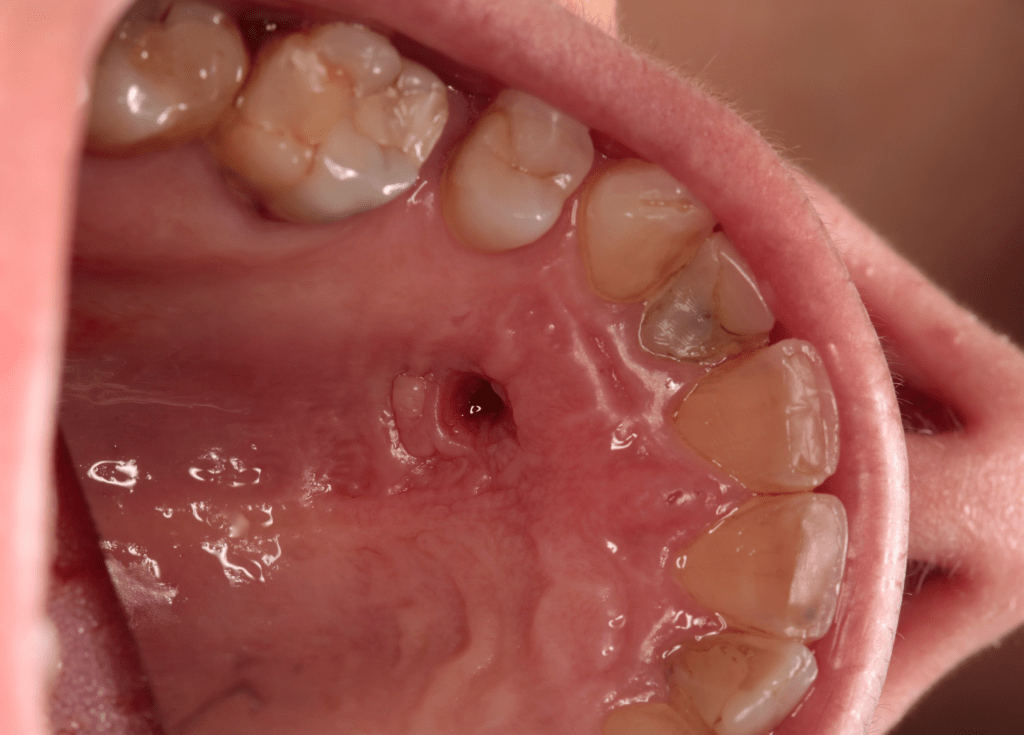

Descompresión por gran lesión